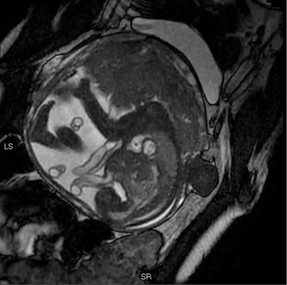

Physiological Fetal Cardiac Anatomy

Pathological Fetal CHD